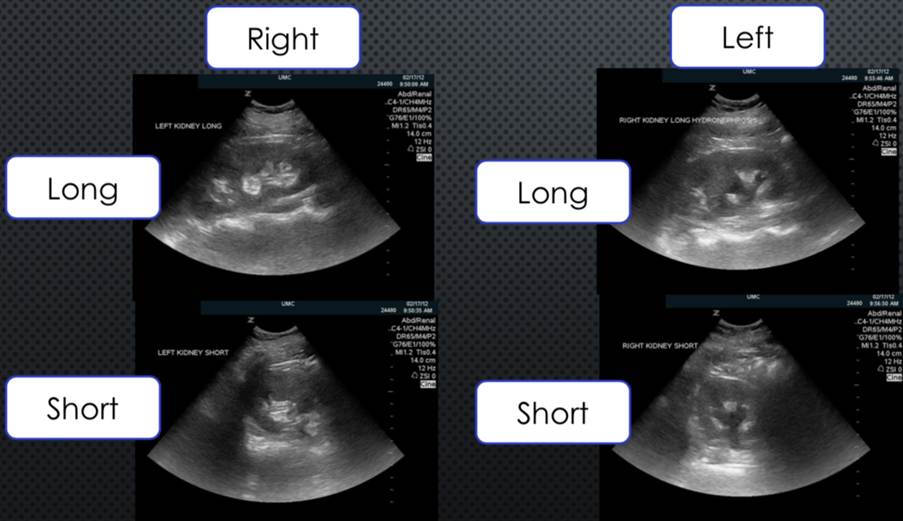

They are often monitored through imaging tests (CT scans and ultrasounds). Small tumours grow slowly and may never be advanced. This is known as active surveillance (American Cancer Society, 2025a).

Figure 2: Ultrasound scan of the kidneys

(Creative Commons, 2025)

This is done as a traditional open surgery and laparoscopic for small, localised tumours or in patients without a scan kidney or in rare cases bilateral renal cancers (Cassidy et al. 2010).

The definition of bilateral is two and if the location where the urine is being collected is swollen, restricted or blocked, this can cause the area to become bigger especially in the tubes (ureter) which limits the amount of urine entering the bladder. This is called bilateral hydronephrosis.